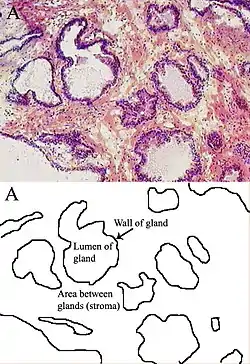

Microanatomy

The prostate consists of glandular and connective tissue.[1] Tall column-shaped cells form the lining (the epithelium) of the glands.[1] These form one layer or may be pseudostratified.[3] The epithelium is highly variable and areas of low cuboidal or flat cells can also be present, with transitional epithelium in the outer regions of the longer ducts.[9] The glands are formed as many follicles, which in drain into canals and subsequently 12–20 main ducts, These in turn drain into the urethra as it passes through the prostate.[3] There are also a small amount of flat cells, which sit next to the basement membranes of glands, and act as stem cells.[1]

The connective tissue of the prostate is made up of fibrous tissue and smooth muscle.[1] The fibrous tissue separates the gland into lobules.[1] It also sits between the glands and is composed of randomly orientated smooth-muscle bundles that are continuous with the bladder.[10]

Over time, thickened secretions called corpora amylacea accumulate in the gland.[1]

Microscopic glands of the prostate

Microscopic glands of the prostate